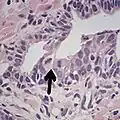

Intraductal carcinoma

This case could meet the criterion of six times normal nuclear size for intraductal carcinoma of the prostate if size is defined as nuclear area but not if defined as nuclear diameter (blue dot: size of normal nucleus, green dot: size six times normal area and red dot: size six times normal diameter).[20]

Intraductal carcinoma of the prostate gland (IDCP), which is now categorised as a distinct entity by WHO 2016, includes two biologically distinct diseases. IDCP associated with invasive carcinoma (IDCP-inv) generally represents a growth pattern of invasive prostatic adenocarcinoma while the rarely encountered pure IDCP is a precursor of prostate cancer.[20] The diagnostic criterion of nuclear size at least 6 times normal is ambiguous as size could refer to either nuclear area or diameter. If area, then this criterion could be re-defined as nuclear diameter at least three times normal as it is difficult to visually compare area of nuclei.[20] It is also unclear whether IDCP could also include tumors with ductal morphology.[20] There is no consensus whether pure IDCP in needle biopsies should be managed with re-biopsy or radical therapy. A pragmatic approach would be to recommend radical therapy only for extensive pure IDCP that is morphologically unequivocal for high-grade prostate cancer.[20] Active surveillance is not appropriate when low-grade invasive cancer is associated with IDCP, as such patients usually have unsampled high-grade prostatic adenocarcinoma.[20] It is generally recommended that IDCP component of IDCP-inv should be included in tumor extent but not grade.[20] However, there are good arguments in favor of grading IDCP associated with invasive cancer.[20] WHO 2016 recommends that IDCP should not be graded, but it is unclear whether this applies to both pure IDCP and IDCP-inv.[20]